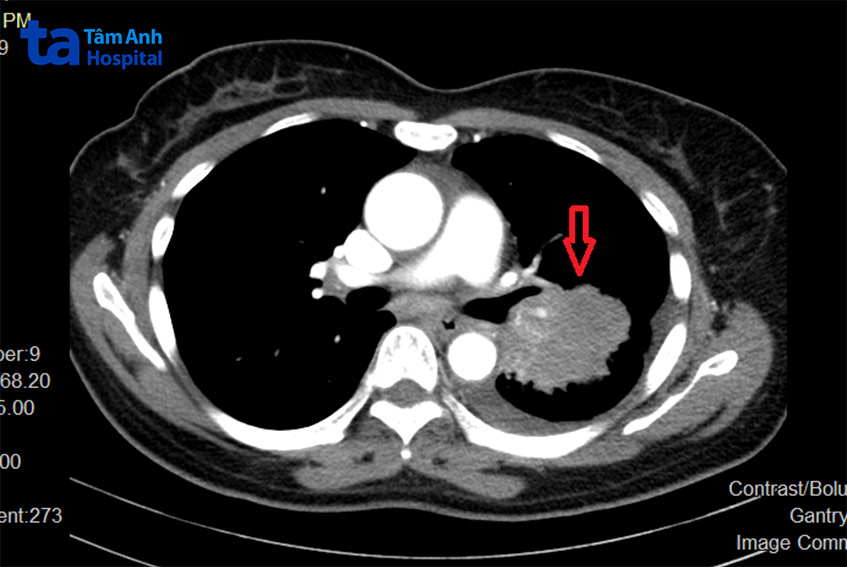

TS.BS Vũ Hữu Khiêm, Trưởng khoa Ung bướu BVĐK Tâm Anh Hà Nội cho biết trên phim chụp cắt lớp vi tính của bà Liên phát hiện nhiều khối u rải rác hai bên phổi, u lớn nhất đường kính 51 x 49 x 35 mm. Bác sĩ sinh thiết khối u, kết quả cho thấy đây là ung thư biểu mô tuyến có đột biến gen EGFR L585R exon 21.

Người bệnh ung thư phổi ở giai đoạn muộn, khối u di căn sang phổi đối bên và gan. Bệnh nhân sau đó được điều trị thuốc đích EGFR TKI. Hiện tại, sức khỏe của bà Liên ổn định, đi lại, ăn uống, sinh hoạt tốt.